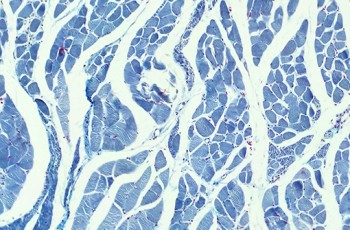

Protagonismo de la salud bucal, y de SEPA, en el 43º Congreso Nacional de... Implicaciones Sistemicas Protagonismo de la salud bucal, y de SEPA, en el 43º Congreso Nacional de... Durante el Congreso se ha destacado la importancia de la salud bucal por su relación con la salud general, apostando... Webinar profundiza en los costes sociales y económicos de la enfermedad... Implicaciones Sistemicas Webinar profundiza en los costes sociales y económicos de la enfermedad... Los costes de la periodontitis se estimaron en 90.000 millones de euros al año, solo por detrás de la diabetes y las... SEPA organiza la primera Cumbre Global de Regeneración Implicaciones Sistemicas SEPA organiza la primera Cumbre Global de Regeneración Del 15 al 25 de septiembre se celebra el “Sepa Regeneration Global Summit”, punto de encuentro para expertos de... Un informe económico muestra que la prevalencia de periodontitis no ha... Implicaciones Sistemicas Un informe económico muestra que la prevalencia de periodontitis no ha... La publicación desvela que el coste financiero y humano derivado de la periodontitis sigue siendo el mismo que hace 20... La división de investigación de The Economist publica un informe... Implicaciones Sistemicas La división de investigación de The Economist publica un informe... Un informe encargado por la EFP revela el impacto económico y social que conlleva la periodontitis y explica cómo una... SEPA ofrece un congreso transversal, integrando un enfoque... Implicaciones Sistemicas SEPA ofrece un congreso transversal, integrando un enfoque... El uso de las nuevas tecnologías y la digitalización en el mantenimiento de la salud bucal son los ejes en los que se... Se anuncia el programa para EuroPerio10 Implicaciones Sistemicas Se anuncia el programa para EuroPerio10 Se ha anunciado el programa científico del congreso EuroPerio10, que tendrá lugar en Copenhague en junio del próximo... Los españoles, a la cabeza de Europa en mejora de salud bucodental... Implicaciones Sistemicas Los españoles, a la cabeza de Europa en mejora de salud bucodental... Un artículo publicado en el último número lanzado de la revista científica... EFP lanzará Implicaciones Sistemicas EFP lanzará La EFP añadirá un enfoque EuroPerio a su portal de formación continua on-line, EFP Virtual, con una serie especial...